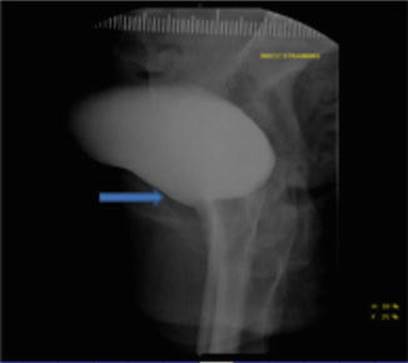

A 65-year-old woman presents with a 1-year history of symptomatic recurrent prolapse following failed trial of pessary. She is status post laparoscopic-assisted vaginal hysterectomy (LAVH) for uterine prolapse and a cystocele repair performed 2 years ago. She reports no SUI. She denies any pain or bowel symptoms. She is G4P3 with all vaginal deliveries. Patient is sexually active and intends to remain active. Examination confirms no leak with cough or strain. No anterior vaginal wall compartment defect is noted (Fig. 16.3), but a large posterior compartment defect is appreciated with POP-Q: Aa −3, TVL −9, C +1, Ap at +1. Vaginal trophicity is adequate with no evidence of ulcerations.

Fig. 16.3

Well supported urethra and bladder base during straining on lateral standing VCUG